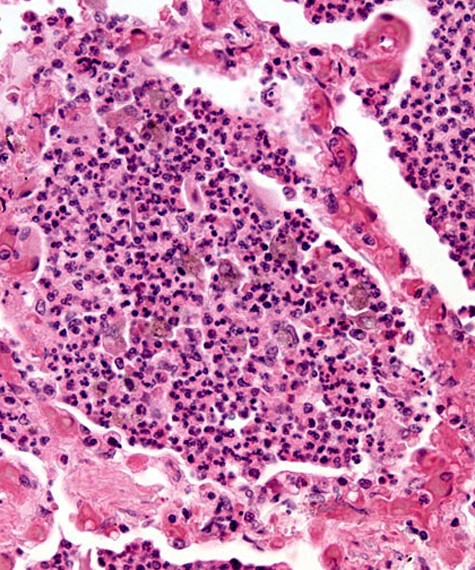

Upon taking my patient’s history, I found that Salamatu presented with a fever, headache, general body weakness and pain, nausea, and vomiting. I requested a Rapid Diagnostic Test (RDT) which came back positive allowing me to diagnose the patient with malaria. I prescribed Salamatu Artemether-Lumefantrine, which is an anti-malarial tablet and advised her to wear long sleeves, pants, and to sleep using an insecticide-treated mosquito net to prevent catching malaria again.